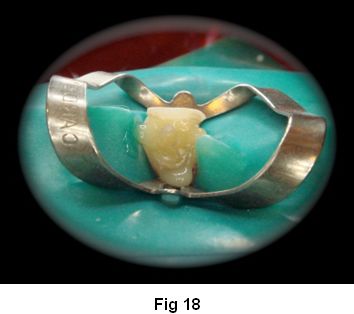

11. Posicionamiento del poste en el conducto (Fig. 18)